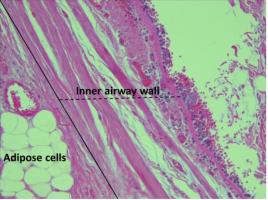

OBÉSITÉ : Elle rétrécit les voies respiratoires et accroît le risque d'asthme